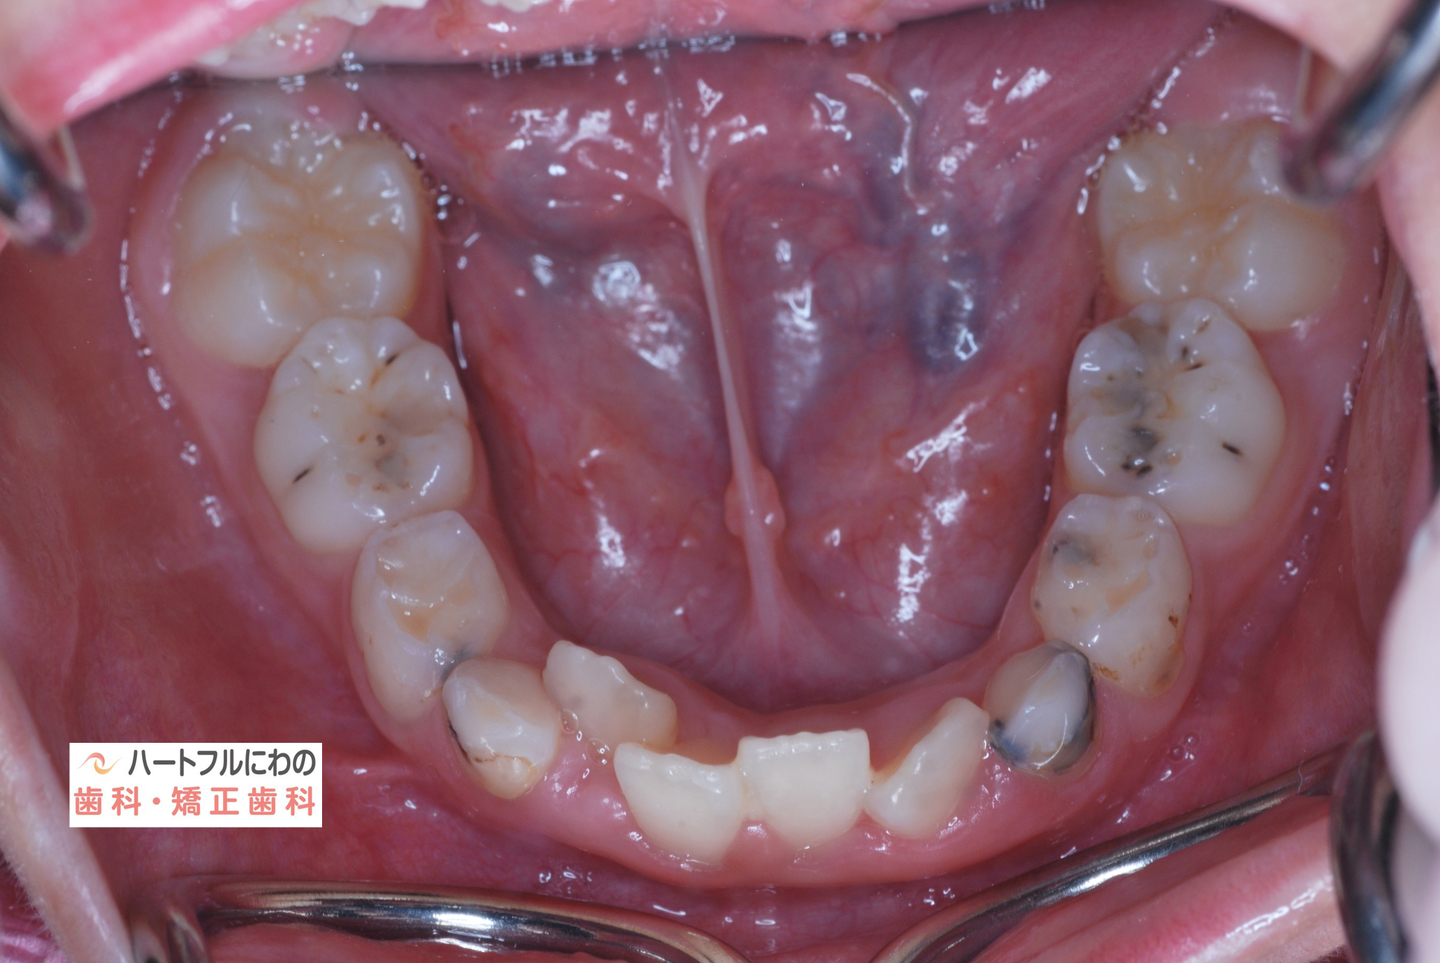

お口の中を拝見すると、上下の叢生(いわゆるガタガタ、乱ぐい)がみられ、多数の虫歯と歯肉炎がみられました。上唇小帯(上唇のすじ)の問題もありました。口呼吸で口腔内が乾燥すると通常の何倍も歯垢が付きやすくなり、虫歯や歯肉炎が頻発します。口呼吸の強い子は重なっている部分のかみ合わせが深い(下の歯がほとんどみえない)のもよく見られる特徴です。

約半年間、成長不全の顎骨を正常に整え、歯の移動も並行して行いました。治療開始から口呼吸の問題は約2か月で大幅に改善、3か月で夜間睡眠は改善し夜尿もほぼなくなりました。それに伴って徐々に他の問題も改善されていきました。小帯に対する外科処置も含めて当院で行うことができます。

その間に食事指導も含め、虫歯や歯周炎の管理も行います。このお子さんは炭酸を含む清涼飲料水が好物でその指導に苦労しましたが、初診時以降は虫歯の発症なく、思春期性の歯肉炎も軽度ですんでいます。

奥歯と前歯の前後的位置関係は大きく改善し、正常になりました。